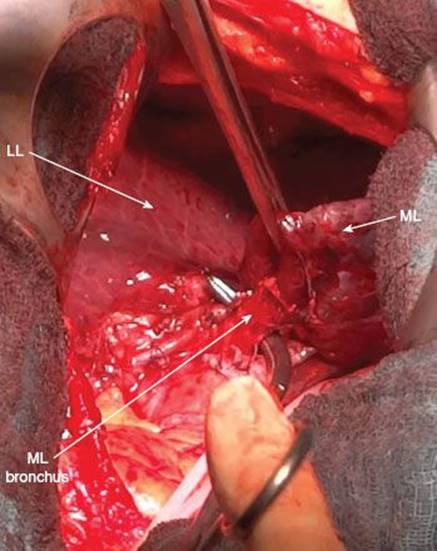

Dissection of Bronchus

Removal of the lymph nodes in the interlobium (station 11) also gives a better exposure of the middle lobe bronchus which lies posteriorly to the middle lobe artery (Fig. 11.9). The bronchus originates from the intermediate bronchus just opposite of the bronchus to the apical segment of the lower lobe (B6). Once the middle lobe artery is transected, the bronchus is clearly visible. It is a rather small structure with the typical cartilaginous impression when palpating. By pulling the middle lobe anteriorly, the bronchus can be identified by placing it between the thumb and index finger. In general the external diameter is not larger than 6 to 7 mm.

Once the bronchus is completely freed from the surrounding tissue, an Overhold clamp can encircle it (Fig. 11.10) and a stapler is passed. The bronchus should be transected close to its origin from the intermediate bronchus. Due to the small diameter of the middle lobe bronchus a medium-size stapler is usually sufficient.

Alternatively, open transsection of the bronchus can be performed with hand sewn closure of the stump. For this maneuvre, the bronchus is held upward with a surgical forceps and dissected with scissors 1 mm off its origin (Fig. 11.11). The advantage of open resection is direct inspection of the resection margin for residual disease, which can also be confirmed by frozen section. If necessary, bleeding from bronchial arteries is punctually coagulated.